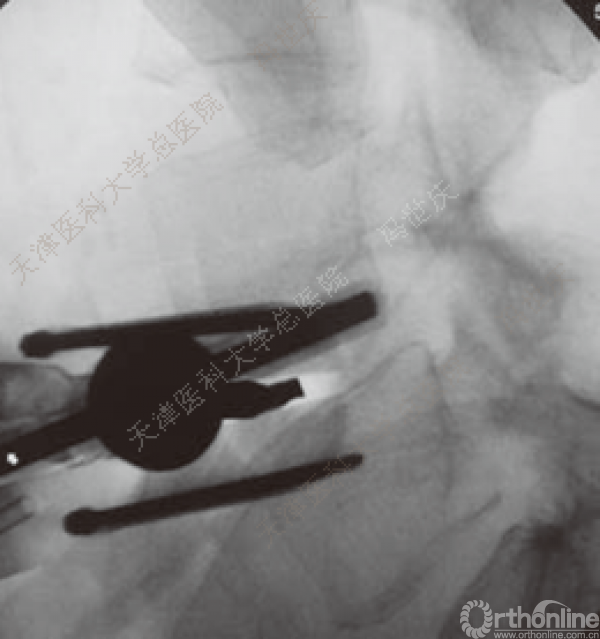

刨刀位于正中

刨刀清扫终板